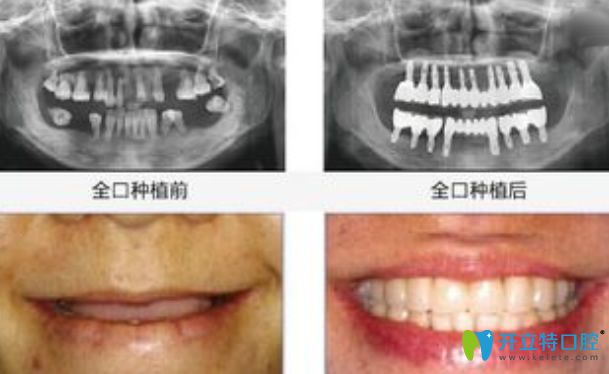

全口種植牙前后對(duì)比圖

牙科醫(yī)生稱一般傳統(tǒng)的種植牙整個(gè)過(guò)程需要三個(gè)階段,大概3-6個(gè)月的時(shí)間,但是目前種植牙并沒(méi)有一個(gè)確定的時(shí)間,這需要根據(jù)牙齒缺失者的身體、口腔、牙槽骨等具體情況來(lái)定,下面就來(lái)看下有關(guān)種植牙的知識(shí):

三、種植體植入3-6個(gè)月后安裝恒久牙冠,牙冠一般采用的是烤瓷材料,其外觀逼真、硬度強(qiáng),非常耐用。